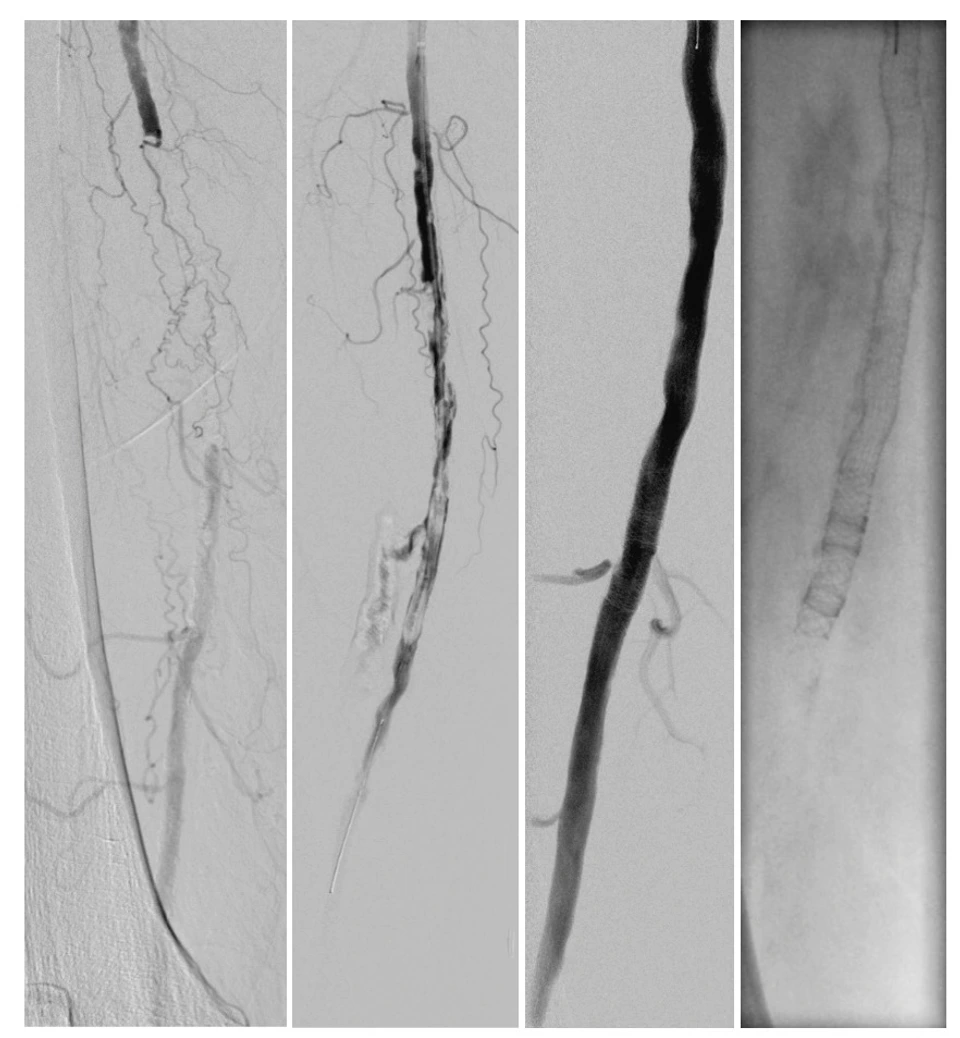

Revaskularisation der Arteria femoralis superficialis

Steiner Lab

Applied Vascular Research

Closeup of a atherosclerosis- 3D rendering

Crack-it Study

Direct Comparison Between Lithotripsy-Based and Standard Lesion Preparation Using Balloon Angioplasty and Subsequent Supera Stent Implantation in Femoropopliteal Lesions with Severe Calcification